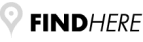

Οφθαλμολογία

Οφθαλμολογία

Το κτηνιατρείο hm vets αναλαμβάνει ψηφιακή ακτινογραφία, έλεγχο δυσπλασίας ισχίου, ορθοπεδική-νευροχειρουργική, χειρουργική μαλακών μορίων, οφθαλμολογία, εσωτερική παθολογία και εργαστηριακές εξετάσεις (αίματος, βιοχημικές, ανοσολογικές, ορμονολογικες, μοριακές και ιστοπαθολογικές).

Το κτηνιατρείο hm vets αναλαμβάνει ψηφιακή ακτινογραφία, έλεγχο δυσπλασίας ισχίου, ορθοπεδική-νευροχειρουργική, χειρουργική μαλακών μορίων, οφθαλμολογία, εσωτερική παθολογία και εργαστηριακές εξετάσεις (αίματος, βιοχημικές, ανοσολογικές, ορμονολογικες, μοριακές και ιστοπαθολογικές).